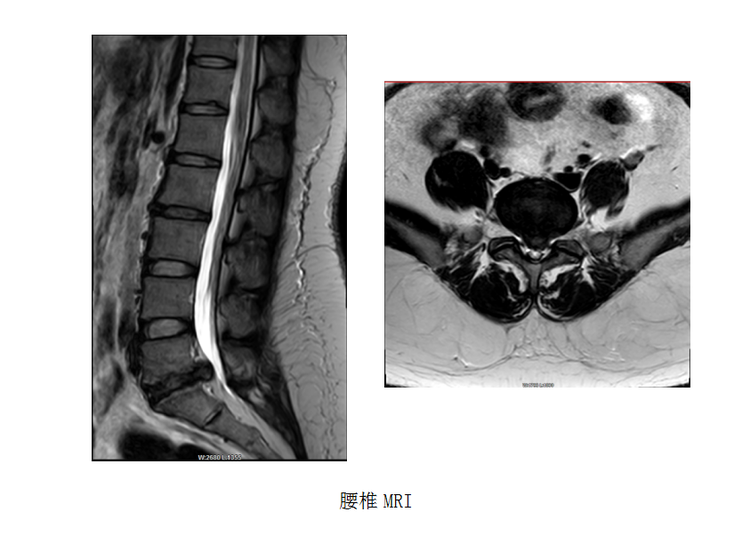

患者,女,28岁,主因“行走时左下肢抽痛1个月”入院。腰椎MRI检查示:腰5骶1椎间盘变性并突出 ,腰5骶1椎体轻度骨质增生并终板炎,腰背部皮下肌筋膜炎。

6月5日对患者行经椎板入路椎间孔镜下腰5骶1髓核摘除+纤维环修复术治疗。